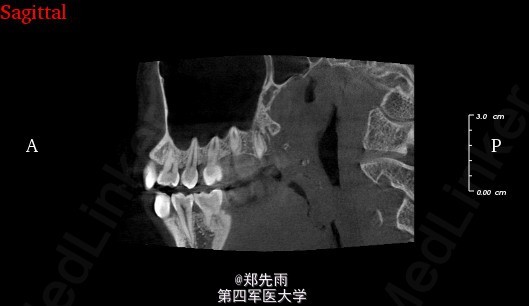

前牙区埋伏牙+上颌窦气化严重

13先天性埋伏阻生,前鼻棘下方埋伏牙,行CBCT检查提示均位于唇侧,但CBCT提示双侧上颌后牙牙根不同程度位于上颌窦内。

诊断:13埋伏阻生,上颌埋伏多生牙。 处理:住院拔除上颌埋伏牙,分次拔除正畸减数牙。与患者术前充分沟通上颌窦穿孔、上颌窦瘘的可能。